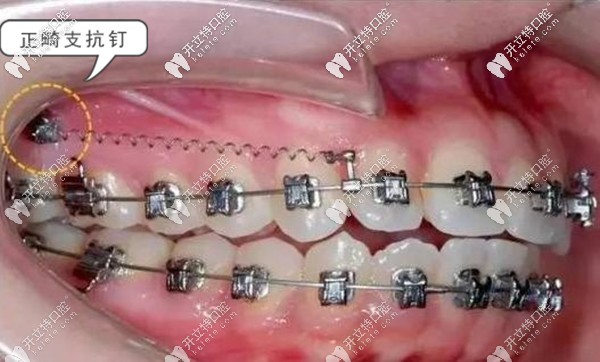

支抗釘——俗稱骨釘,支抗釘主要是拉間隙調(diào)整牙位,也就是借力用的。支抗骨釘不但可以解決牙齒的深覆合咬合問題,也可以讓矯正過程中的牙齒移動(dòng)更快,還可以改善露齦笑、齙牙等問題。

牙齒矯正支抗釘?shù)淖饔? border=